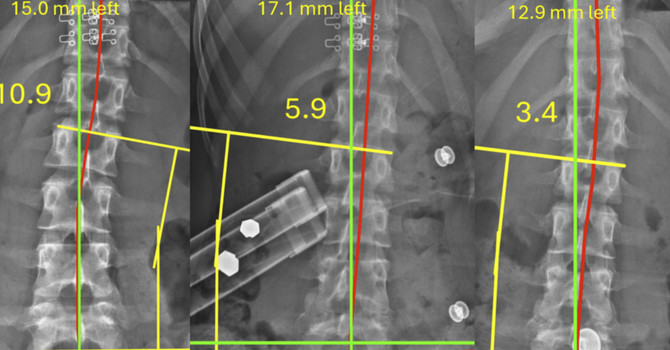

• Radiographic Sagittal Alignment and Kinetic Chain Alterations in Geriatric Patients with Scoliosis: A Case Series

Kinetic Chain Dysfunction in Geriatric Scoliosis image

Kinetic Chain Dysfunction in Geriatric Scoliosis

Kinetic Chain Dysfunction in Geriatric Scoliosis: What the Research Shows